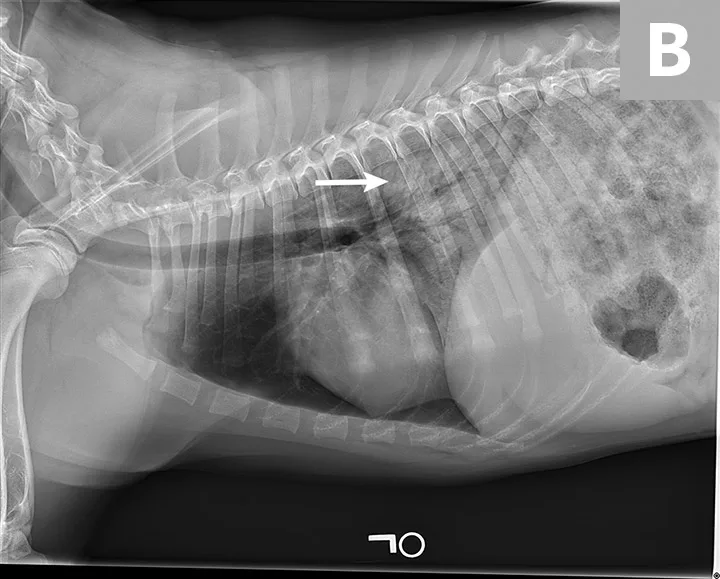

Blood pressure was decreased (85 mm Hg) on Doppler ultrasound. Oxygen saturation was initially 92% but increased to 98% with flow-by oxygen supplementation via mask (4 L/minute). Initial blood work showed mild hyperlactatemia (3.1 mmol/L; reference range, 0-2.5 mmol/L), packed cell volume of 54%, and total solids at 6.8 g/dL. Chest radiography was performed with oxygen supplementation and revealed a moderate to severe caudodorsal interstitial to alveolar lung pattern (Figures 1 and 2).

Radiograph showing air bronchograms consistent with noncardiogenic pulmonary edema (arrows). Atelectasis, which would be evident with shifting of the heart to the left or right, is not present.

Radiographs showing caudodorsal alveolar pattern consistent with noncardiogenic pulmonary edema (arrows). Edema is caudodorsal and bilateral. The heart size is normal, and there is no elevation of the airways that would indicate left-sided heart enlargement. Sternal contact of the heart, which might suggest right-sided heart enlargement, is minimal.